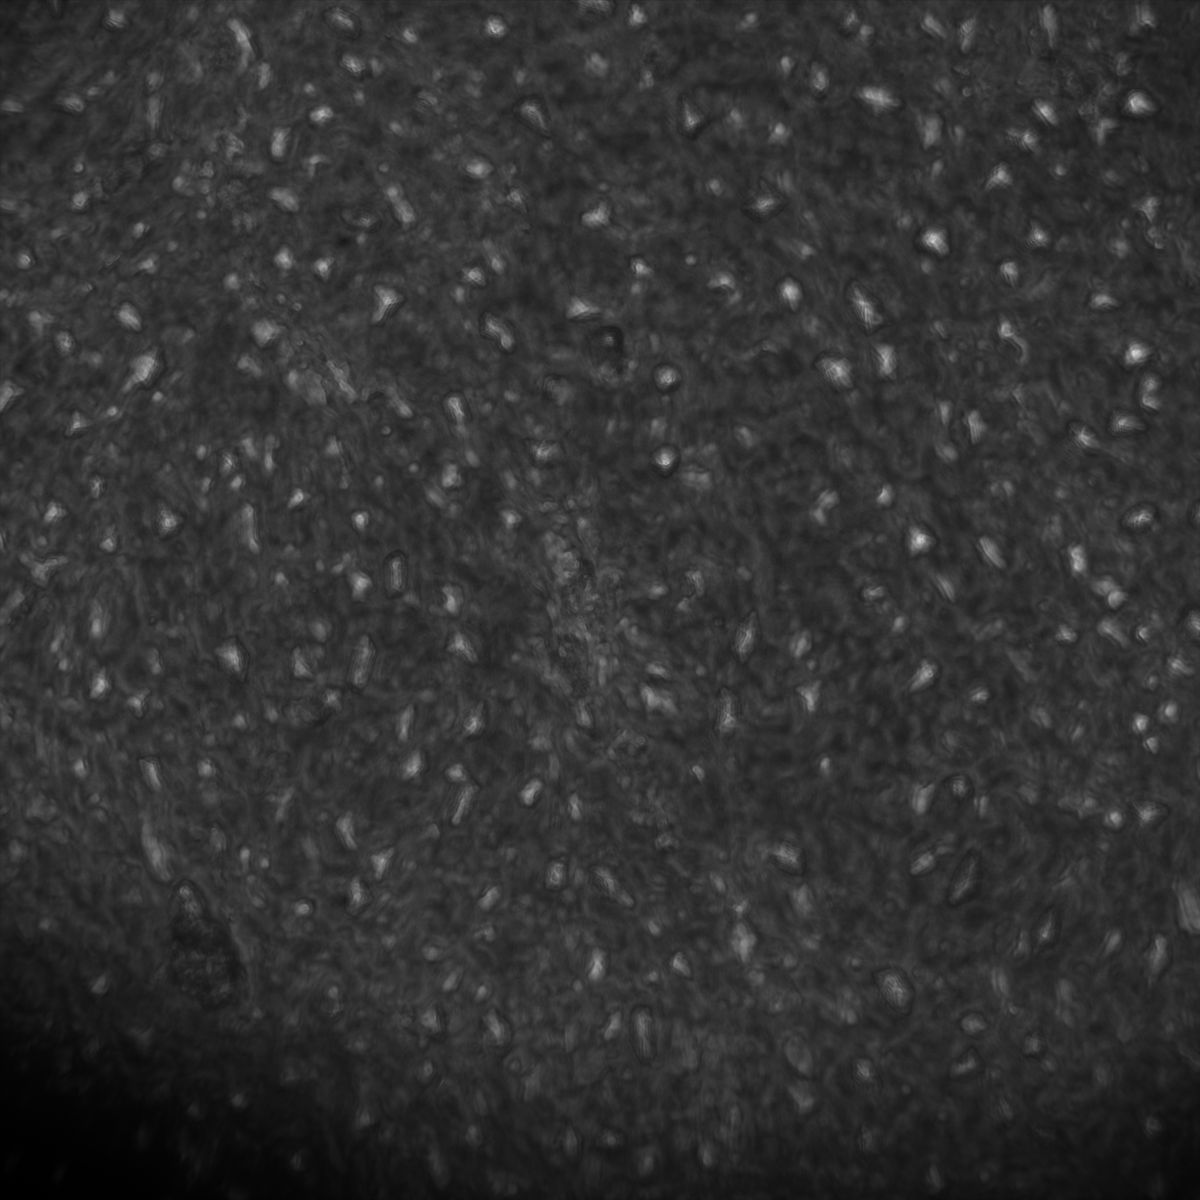

Actin